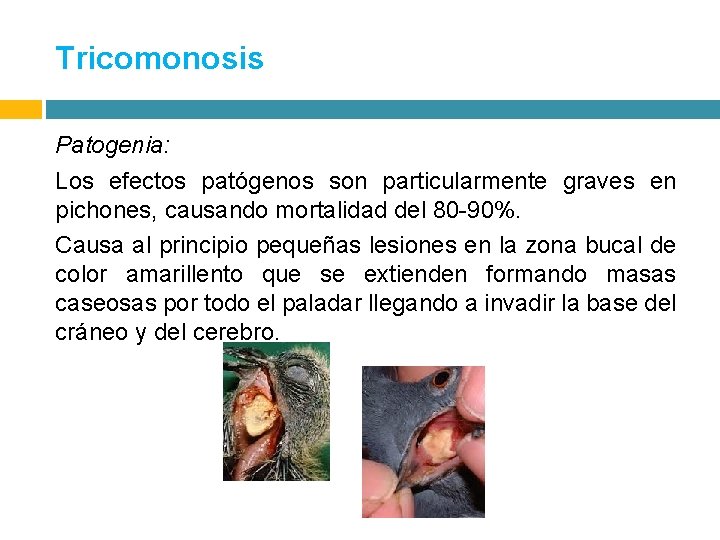

Tricomonosis Patogenia: Los efectos patógenos son particularmente graves en pichones, causando mortalidad del 80 -90%. Causa al principio pequeñas lesiones en la zona bucal de color amarillento que se extienden formando masas caseosas por todo el paladar llegando a invadir la base del cráneo y del cerebro.